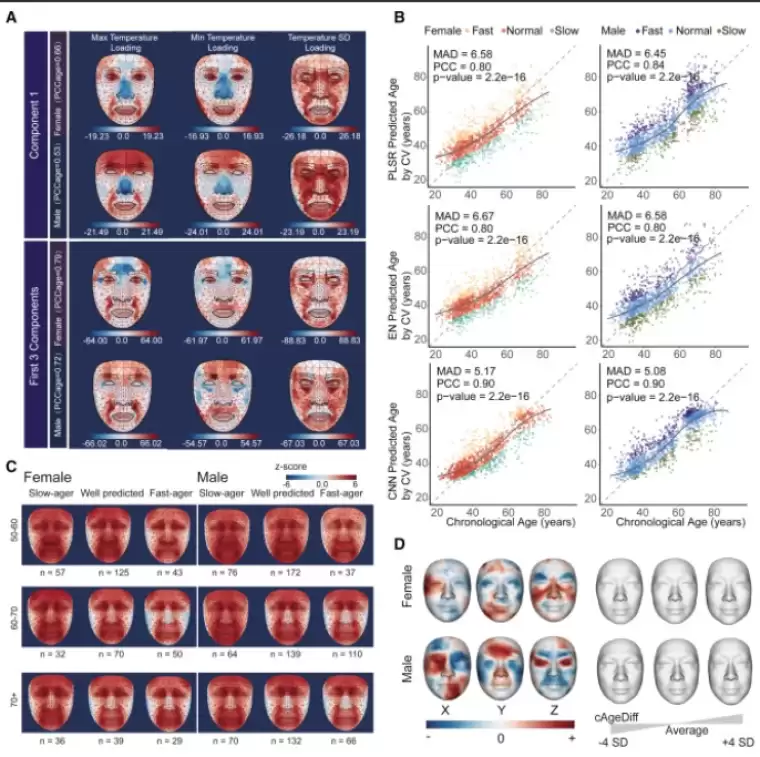

NTV'nin aktardığı habere göre; araştırmacılar, yaklaşık 2 bin 800 Çinli katılımcının yüzlerinin termal fotoğraflarını çekerek 54 farklı noktada sıcaklık analizi yaptılar. Ulaşılan veriler ile eğitilen yapay zeka modeli, katılımcıların biyolojik yaşlarını sıcaklık değişimlerine göre tahmin etmekte kullanıldı. Özellikle burun ve yanakların soğumasının yaşlanmayla ilişkilendirildiği gözlemlendi.

Çalışma, diyabet ve karaciğer hastalığı gibi metabolik bozuklukların, göz çevresinde sağlıklı bireylerle kıyaslandığında daha yüksek sıcaklıklara neden olduğunu ortaya koydu. Bu bulgular, termal yüz görüntülemenin hastalıkların erken teşhisi için potansiyel bir araç olabileceğini gösteriyor.

Egzersizle Termal Yaş Azalıyor

Araştırmacılar, günde en az 800 kez ip atlamayı içeren 2 haftalık bir egzersizin katılımcıların termal yaşlarını beş yıl azalttığını belirledi. Bu bulgu, sağlıklı yaşam alışkanlıklarının biyolojik yaş üzerinde olumlu etkisi olduğunu gösteriyor.